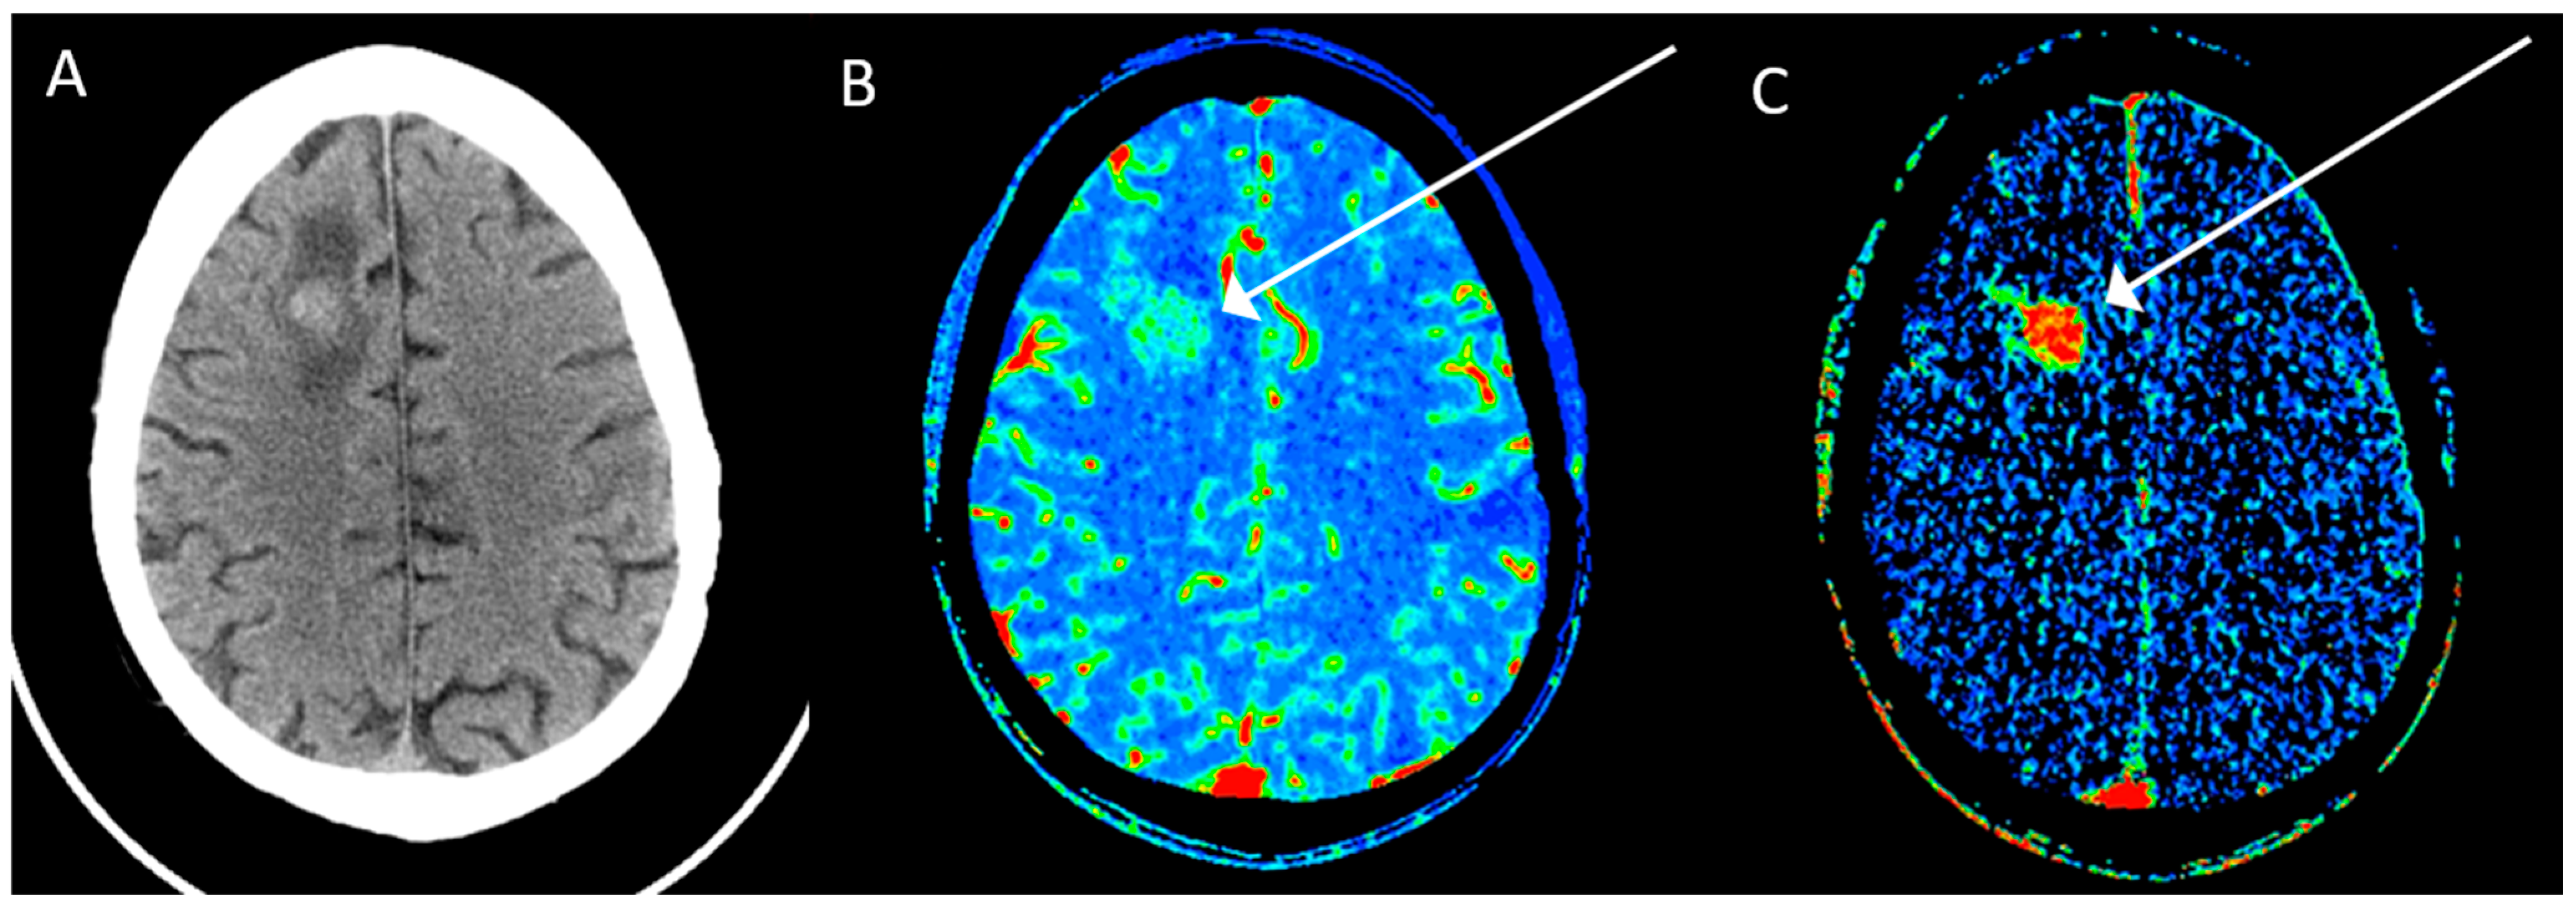

- Onishi, S.; Kajiwara, Y.; Takayasu, T.; Kolakshyapati, M.; Ishifuro, M.; Amatya, V.J.; Takeshima, Y.; Sugiyama, K.; Kurisu, K.; Yamasaki, F. Perfusion Computed Tomography Parameters Are Useful for Differentiating Glioblastoma, Lymphoma, and Metastasis. World Neurosurg. 2018, 119, e890–e897. [Google Scholar] [CrossRef]

- Shankar, J.J.; Woulfe, J.; Silva, V.D.; Nguyen, T.B. Evaluation of perfusion CT in grading and prognostication of high-grade gliomas at diagnosis: A pilot study. Am. J. Roentgenol. 2013, 200, W504–W509. [Google Scholar] [CrossRef] [PubMed]